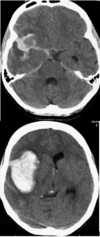

Neurokirurgisk vagthavende beder dig om at foretage ny CT scanning.

Billederne - 2 forskellige snit af samme scanning - viser.

Forskellen på den tidligere normale CT scanning og den nye CT scanning er:

a. Tilkomst af SAH

b. Tilkomst af SAH og intracerebralt hæmatom

c. Tilkomst af SAH og epidural blødning

d. Tilkomst af SAH og subduralt hæmatom

*b. Tilkomst af SAH og intracerebralt hæmatom